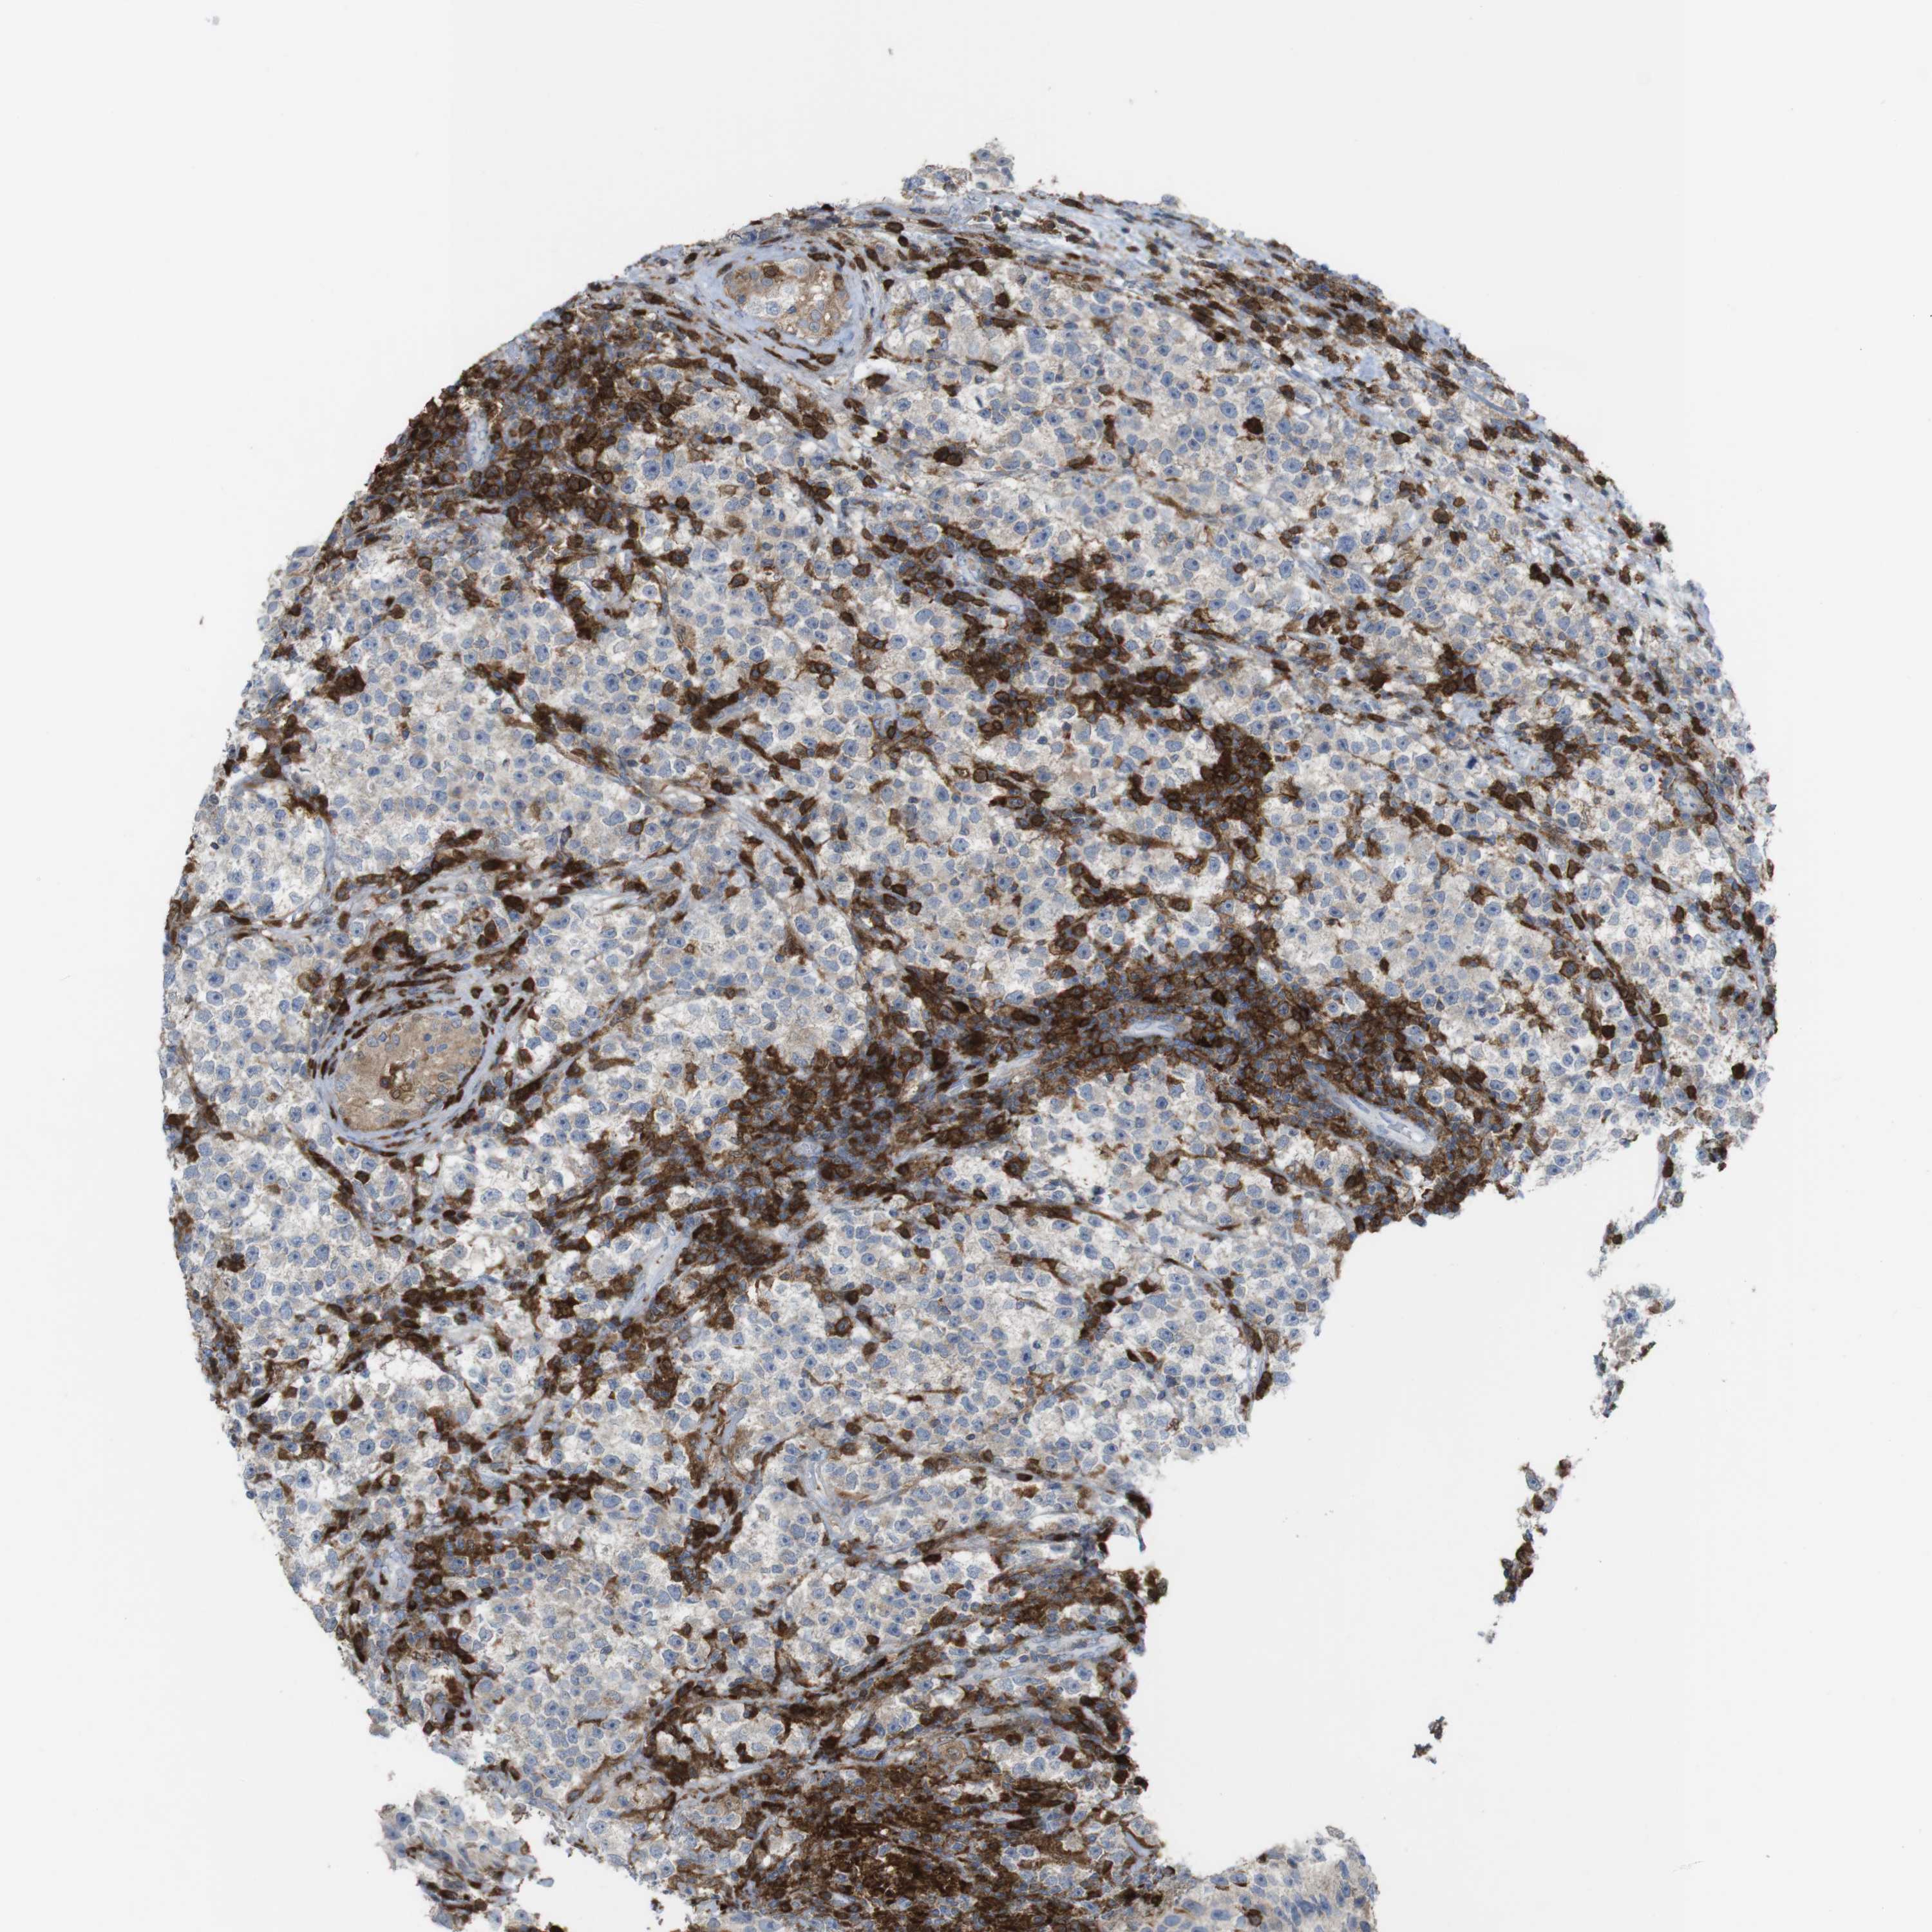

TESTIS CANCER - Protein expressioni

A mouse-over function shows sample information and annotation data. Click on an image to view it in a full screen mode. Samples can be filtered based on level of antibody staining by selecting one or several of the following categories: high, medium, low and not detected. The assay and annotation is described here.

Note that samples used for immunohistochemistry by the Human Protein Atlas do not correspond to samples in the TCGA dataset.

Antibody stainingi

Antibody staining in the annotated cell types in the current human tissue is reported as not detected, low, medium, or high, based on conventional immunohistochemistry profiling in selected tissues. This score is based on the combination of the staining intensity and fraction of stained cells.

Each image is clickable and will lead to virtual microscopy that enables deeper exploration of all samples and also displays staining intensity scores, fraction scores and subcellular localization as well as patient and tissue information for each sample.

Antibody HPA001890

Seminoma, NOS